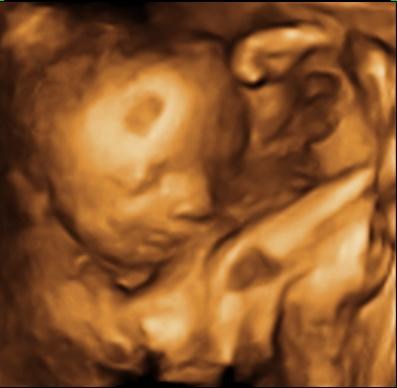

Så var vi i går den 20 jan til 3D/4D scanning af lillepigen, desværre blev der kun få rimelige billeder da hun ikke lå særlig godt, og samtidig blev ved at dække ansigtet med arme og ben

Vedhæftede fotos (klik for at se i fuld størrelse)

På det sidste billede ser det ud til at hun smågriner/smiler af jer. Hun er da allerede en drillepind